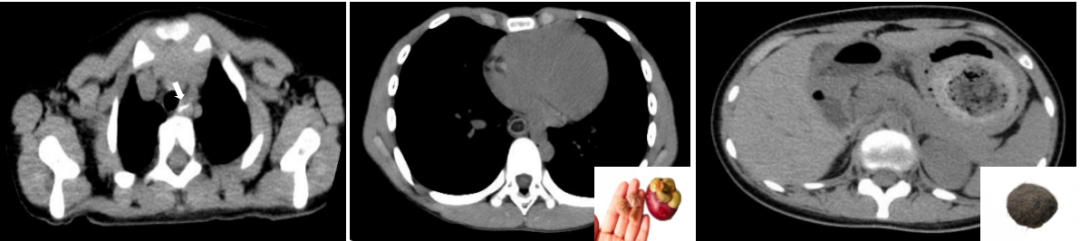

正如侦探破案需多方取证,X线也有其“盲区”。对于“透X线”的物体,它们在X线下几乎不显影,例如:

①食物类:鱼刺、细小骨头、果核。

②木质物品:如牙签、木屑。

③薄塑料或硅胶制品:如部分玩具碎片、小胶囊盖。

这类异物若怀疑残留,可能需要借助CT扫描或内镜检查进一步明确。

CT扫描下的异物(从左到右:碎骨、山竹核、毛发团)